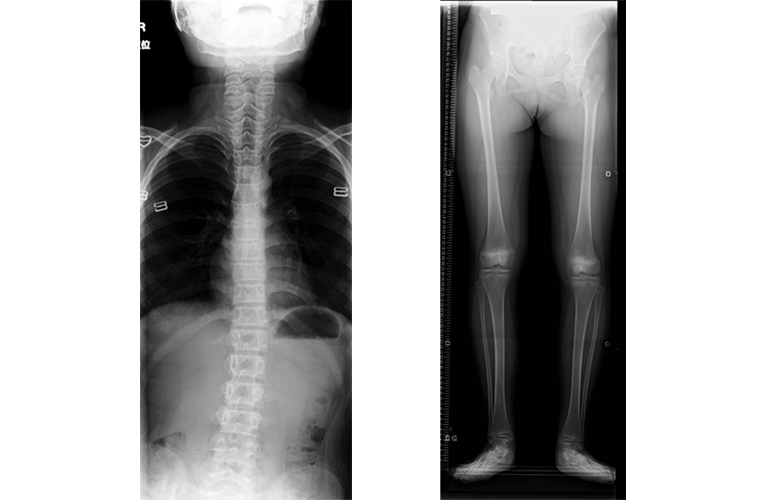

脚長不等(左右の脚の長さの違い)による機能性側弯症。足底板で左右の脚の長さを整えると側弯は消失する。